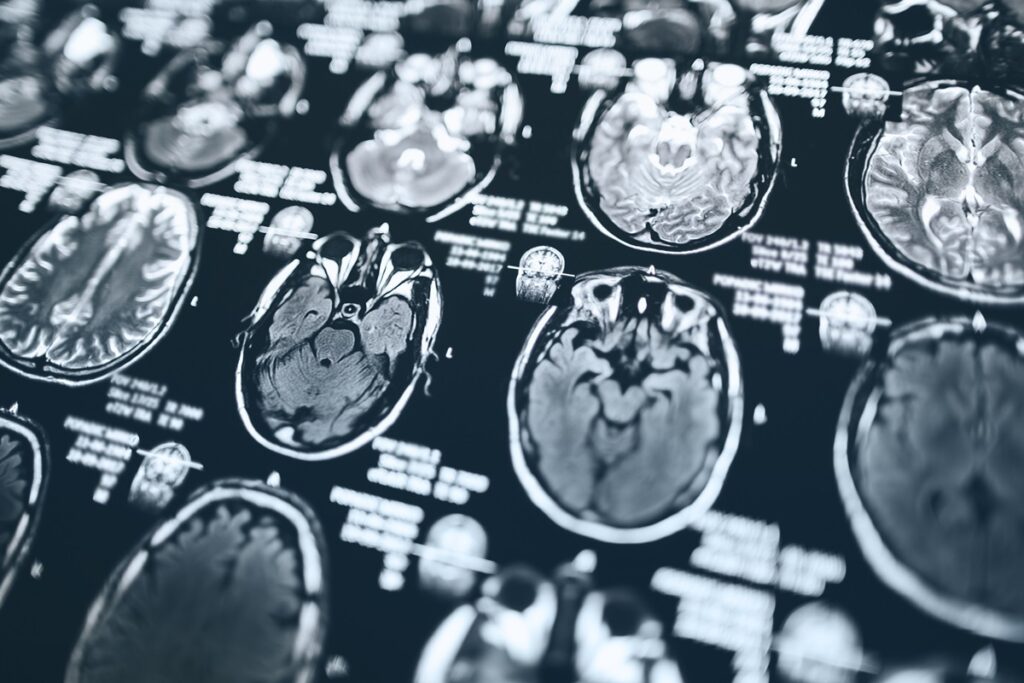

- O Alzheimer é uma doença que afeta o funcionamento do cérebro de forma progressiva, prejudicando a memória e outras funções cognitivas.

O medicamento, da empresa Eli Lilly, atua eliminando placas de beta-amiloide, proteínas que se acumulam no cérebro e estão associadas à perda de memória e declínio cognitivo.